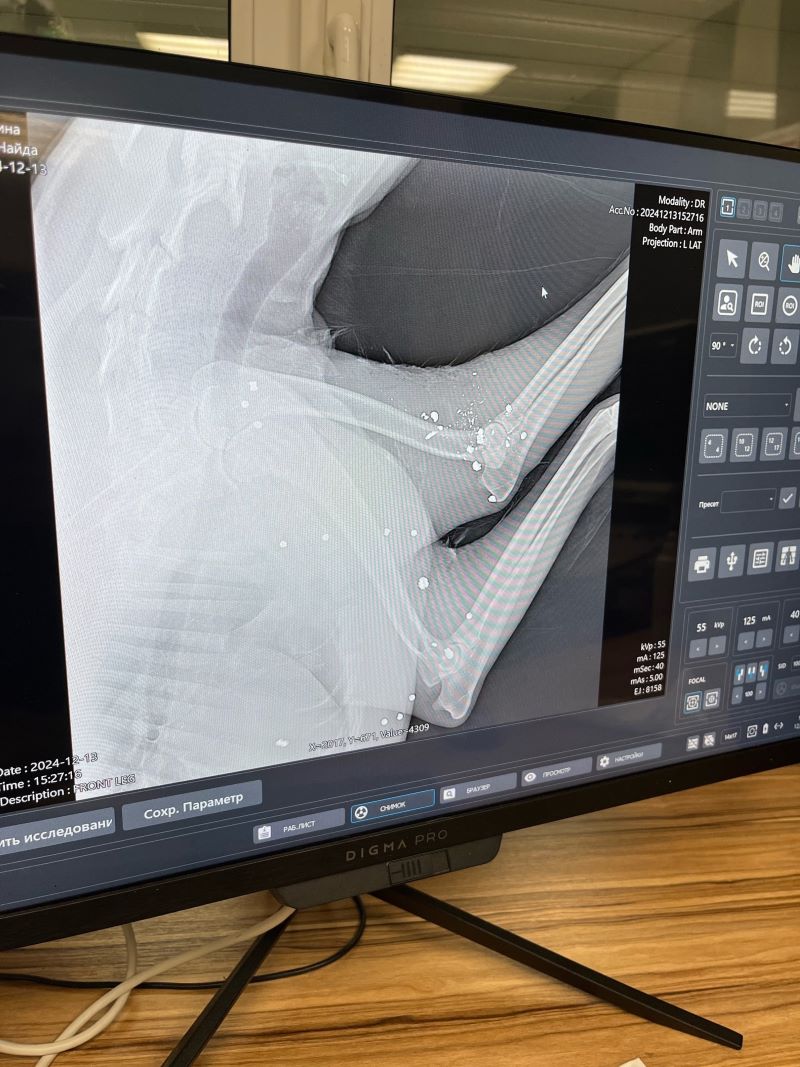

В редакцию портала« маленькая Сызрань» обратилась женщина, которая сообщила о страшном инциденте. В пятницу, 13 декабря, примерно с 10.00 до 12.00 в районе села Троекуровка неизвестным из оружия была расстреляна собака. По предварительной версии, это был охотник, который стрелял с дороги. Собака, которая живет в поселке с рабочими не была безнадзорной, но по стечению обстоятельств именно в этот день она выбежала на трассу и оказалась на обочине. Как сообщила автор, рентген показал, что тело собаки испещрено пулями. У собаки остались щенки. Автор сообщила, что сельчане намерены написать заявление в полицию. Пока люди ищут свидетелей.

Фото: фото предоставлены порталу Маленькая Сызрань Данилой М.